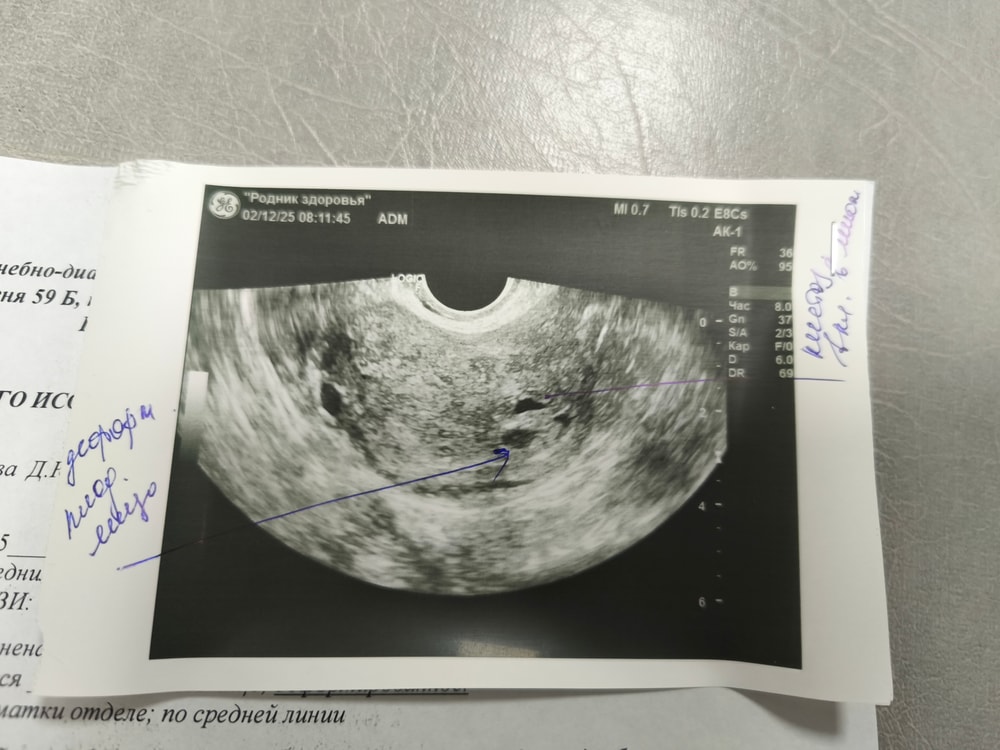

Джеллибин, вот сейчас я вам покажу, они даже с разных сторон находятся Изображение Это сегодня , ниже в первый день задержки Изображение

0

Буду трижды мамой в этом году, отправляют из за того что нет желточного мешочка и деформировано пя

Диана , деформировано оно может быть из- за тонуса. Он может появиться позже, у вас срок маленький. Подруга неделю назад ходила на узи, срок по месячным был 6+2нед. было пя только 9 мм и всё. Сегодня сходила, появился жм и зачаток эмбриона. Поэтому рано ставить такие диагнозы, минимум неделю надо подождать и переделать узи и уже потом делать окончательные выводы